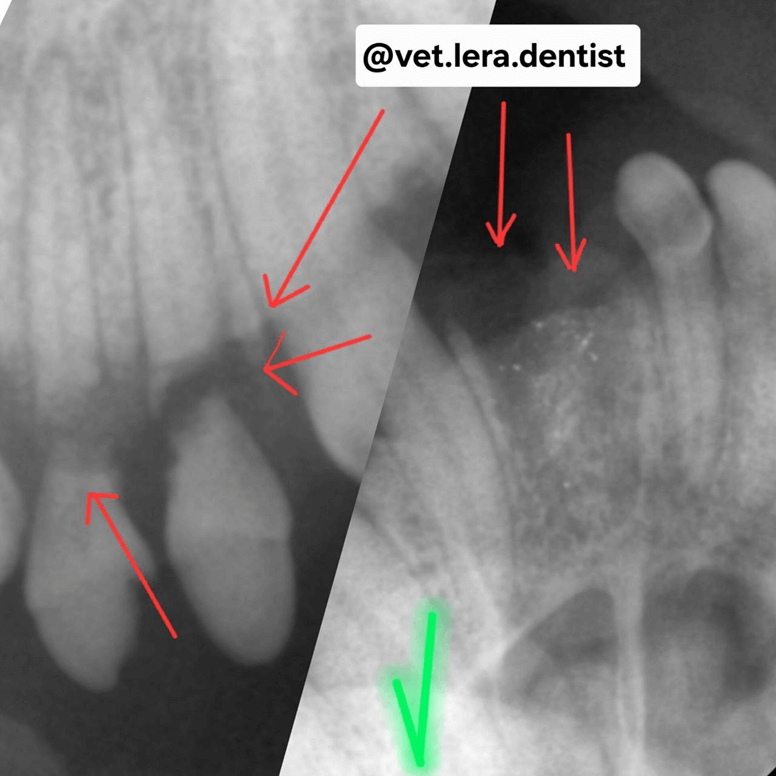

1-12-25092025.png

Фото 11. Терьер. 12 лет.

У пациента гнойный пародонтит, но также было обнаружено поражение кариесом (красные стрелки) — затрагивающие пульпарную камеру.

Терапия. Кариозные повреждения, не затрагивающие пульпу, лечатся удалением инфицированных тканей с последующей реставрацией. В случае когда кариозные повреждения затрагивают пульпарную камеру — проводится эндодонтическое лечение, однако чаще всего такой зуб удаляется.